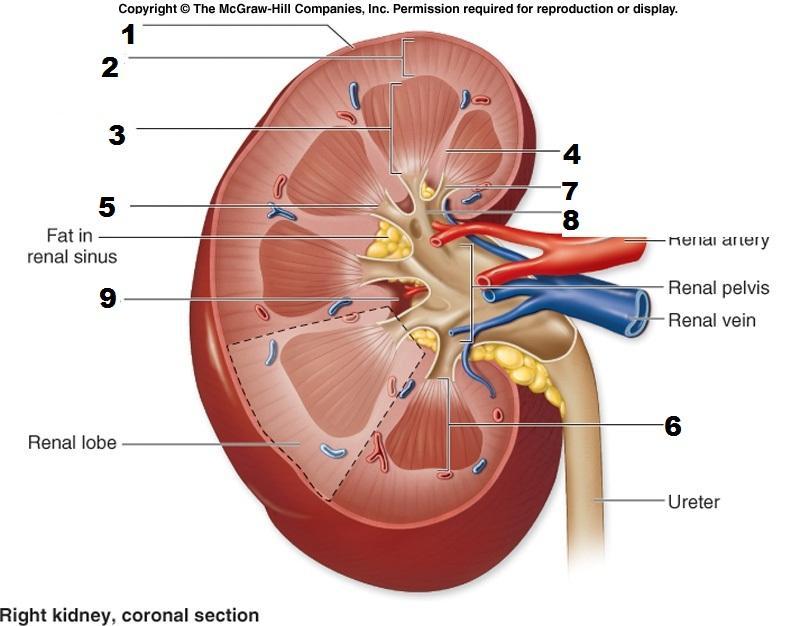

Calyx (of the kidney)

Kidney

Medullary pyramids

Renal artery/vein

Renal capsule

Renal columns

Renal cortex

Renal medulla

Renal Pelvis

Ureter